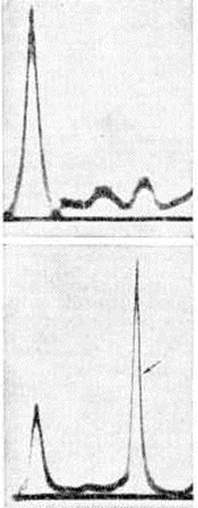

При исследовании крови в начале заболевания выявляется ускоренная РОЭ, что связывают с преобладанием в плазме грубодисперсных белков (парапротеинов), которые выявляют с помощью электрофореза (рисунок 7). Принадлежность парапротеина к одному из классов Ig определяют с помощью иммуноэлектрофореза (смотри полный свод знаний) с моноспецифическими антисыворотками (рисунок 8) или радиальной иммунодиффузии на агаровом геле по Манчини (смотри полный свод знаний Иммунодиффузия.); последний метод применяют также для количественного определения парапротеинов. Этими же методами и с помощью простой диффузии на агаре, при использовании моноспецифических антисывороток против К и X лёгких цепей, определяют тип лёгких цепей Ig. Для Миеломная болезнь характерно снижение (депрессия) концентрации иммуноглобулинов, не относящихся к парапротеину (так называемый «не-М-компоненты», или физиологический иммуноглобулины), с чем связывают нарушение гуморального иммунитета.